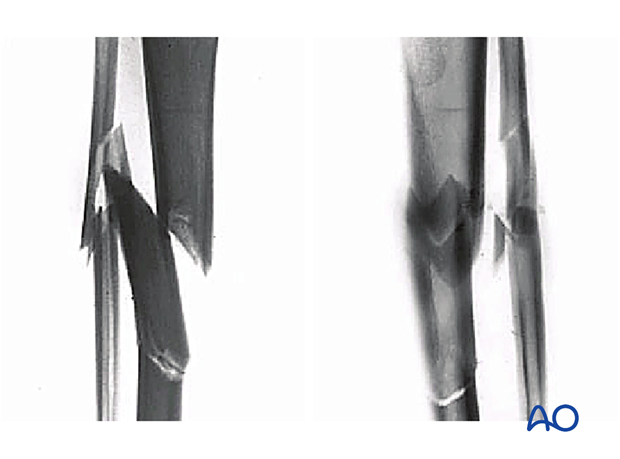

This x-ray reveals an intact segmental, multifragmentary fracture of the tibia and fibula.